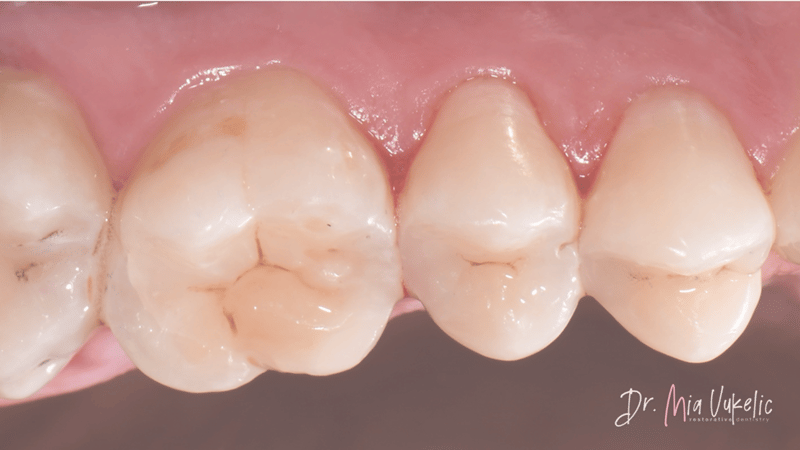

After proper isolation with a rubber dam and placement of wedges, the cavity preparation began with a cylindrical bur. Following the removal of the restoration, we proceed to eliminate demineralized dentin using a steel bur. The final cavity refinement involved converting convergent walls into divergent ones and polishing the internal cavity surface with diamond polishing burs.

![]() |